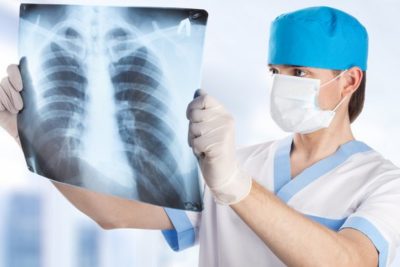

На снимке, сделанном в трех проекциях (прямая, боковая и косая) обнаруживаются характерные участки затемнения. В сложных и сомнительных случаях необходимо наложить искусственный пневмоторакс и пневмоперитонеум или провести компьютерную томографию легких.

Если осумкованный плеврит существует в течение длительного времени, он может повлиять на состояние легочной паренхимы.

Чтобы оценить изменения в ней, следует провести бронхографию – снимок бронхов с контрастом, и ангиопульмонографию – рентгенографическое исследование сосудов легочной ткани с предварительным введением контрастного вещества.

С помощью УЗИ можно оценить количество экссудата и его характер, а также определить наилучший доступ для удаления этой жидкости. Еще один метод обследования – плевральная пункция с последующим лабораторным исследованием выпота. Она позволяет достоверно поставить диагноз. В некоторых случаях целесообразно провести торакоскопию и биопсию плевры.